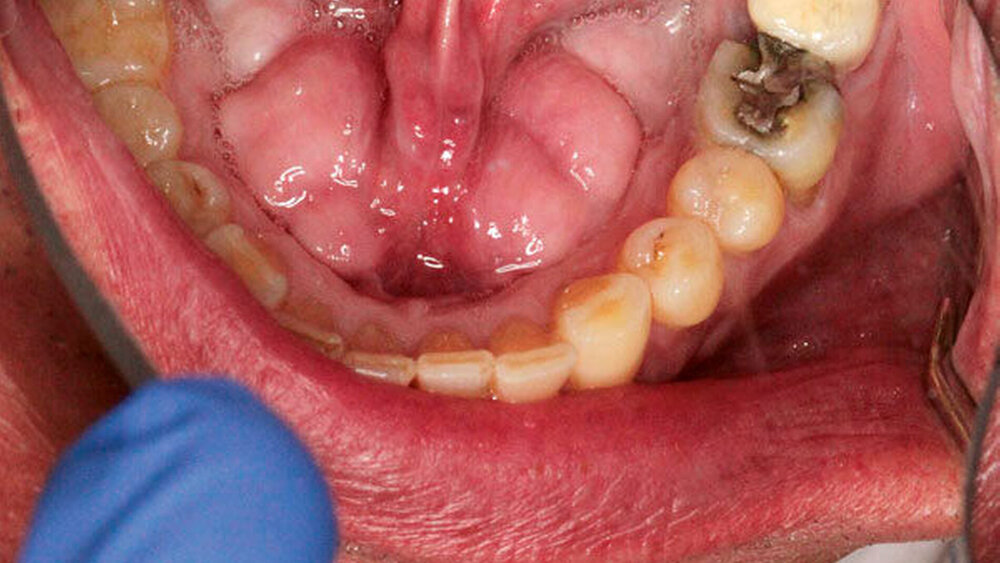

Klinisch präsentierte sich der Patient in gutem Allgemein- und Ernährungszustand ohne auffällige Familienanamnese. Bei der oralen Inspektion imponierten zwei Raumforderungen im Unterkiefer lingual beidseits mit einer Adhärenz zum Alveolarkamm (Abbildung 1). Auf Palpation gab der Patient keine Schmerzen an. Es bestanden keine Gefühls- oder Geschmacksstörungen.

Zur erweiterten Diagnostik wurde eine Digitale Volumentomografie (DVT) angefertigt. Diese zeigte zwei lingual gelegene knöcherne Auftreibungen mit einer Ausdehnung von der Unterkieferfrontzahnregion bis zu den Molaren (Abbildung 2). Nebenbefundlich zeigte sich ein nicht erhaltungswürdiger Zahn 36. Bei unauffälliger Anamnese, fehlender B-Symptomatik sowie einem langsamen und verdrängenden Wachstum wurde die Verdachtsdiagnose eines Torus mandibularis gestellt.